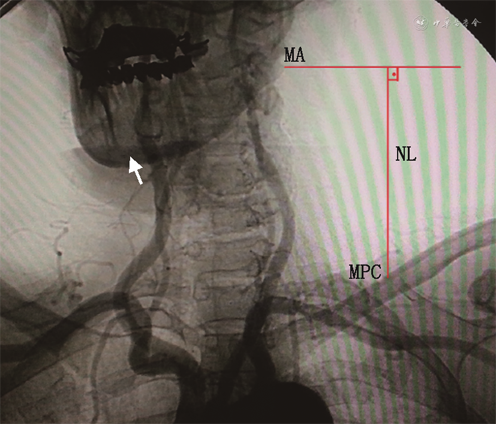

2. 颈动脉DSA相关数据获取方法:在DSA室无菌操作台下进行。局部麻醉后,穿刺股动脉或者桡动脉,先行主动脉弓上血管造影。随后导管分别超选入左、右侧颈动脉,行颈动脉3D造影。影像数据保存在CT工作站,经图像测量获得所需参数。(1)按颈动脉分叉位置对应颈椎水平:分为C2、C2~C3、C3、C3~C4、C4、C4~C5、C5(图1);(2)测量颈长:下颌角到锁骨中点的垂直距离定义为颈长(图2);(3)颈内动脉形态定义与分类:参考Weibel和Fields[3]的颈内动脉颈段走形异常分类标准,即根据扭曲程度分为3类:迂曲:指颈动脉非线性延伸成钝角;扭曲:指颈动脉扭曲成1个或多个锐角;盘曲:指颈动脉以横轴盘绕成1个袢(图3);该分类方法简便易行,能直观反映扭曲的严重程度。本研究根据颈内动脉扭曲程度,将颈内动脉形态分为颈内动脉扭曲组(包括颈内动脉扭曲和盘曲)和颈内动脉非扭曲组(包括颈内动脉正常和迂曲)。

注:MA为下颌角;NL为颈部长度;MPC为锁骨中点

3.颈动脉超声相关数据获取方法:采用彩色多普勒超声诊断仪高频线阵探头扫查,患者取平卧位,颈后及双肩垫高,头后仰10°~20°,转向检查对侧约30°~45°,充分暴露颈前区。探头放置于颈部前方、外侧,自下而上依次扫查,分别进行横切面和纵切面检查,观察颈总动脉、颈内动脉、颈外动脉。从锁骨上缘自近心端向远心端横切扫描颈总动脉,当显示由颈总动脉分出颈内动脉和颈外动脉时,再转为纵切,使分叉点位于探头长度的中点,于该皮肤处用标记笔描记,用软尺测量分叉点至下颌角距离,测量3次取平均值。参考Wain等[4]对颈动脉分叉高低的定义,颈动脉分叉至下颌角距离≤1.5 cm为高分叉,颈动脉分叉至下颌角距离>1.5 cm为正常分叉(图4)。